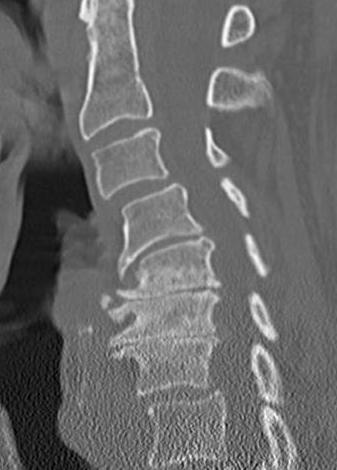

CT scan

2 level disc degeneration on CT